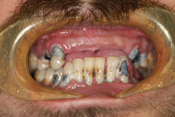

WORST TEETH Pictures from Warren Dentistry

This can happen to your teeth when proper Dental Hygiene is not practiced.

Patient 1